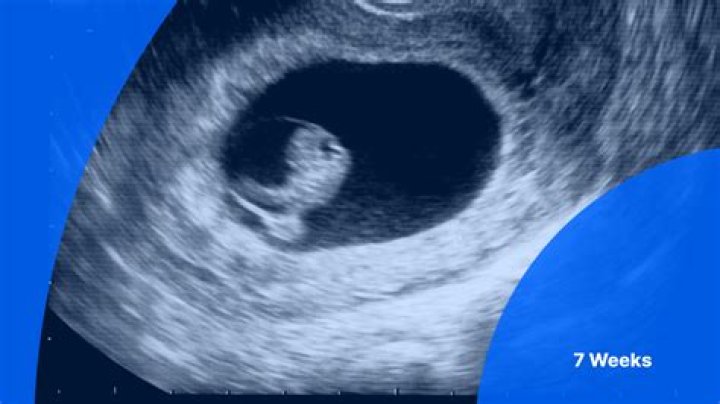

A normal heartbeat at 6-7 weeks would be 90-110 beats per minute. The presence of an embryonic heartbeat is an assuring sign of the health of the pregnanc...